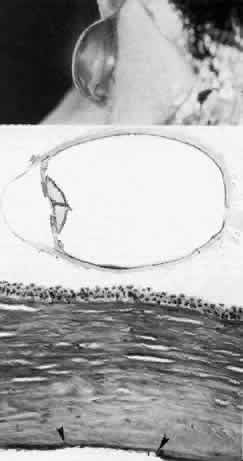

Among the classic corneal dystrophies, macular dystrophy, unlike granular and lattice dystrophies, is an autosomal recessive disorder and is far less common. It usually begins in the first decade of life and leads to progressive visual deterioration as the stroma becomes generally cloudy, with superimposed dense, gray-white spots (Figs. 5 AND 11; Color Plate 1H). Unlike granular dystrophy, these macular spots have indefinite edges and the intervening stroma is not clear. Young patients exhibit axial lesions in the superficial layers of the cornea, but with time, lesions approach the periphery and extend throughout the entire stromal thickness. Corneal thinning confirmed by central pachymetry has been documented.129 Also unique is primary involvement of the endothelium as evidenced clinically by the presence of guttate changes of Descemet's membrane.

Fig. 11. Macular corneal dystrophy. Top left. Clinical appearance of cornea features diffuse haze extending to the limbus with superimposed, dense gray-white spots. Bottom left. Light photomicrograph of posterior cornea shows endothelial cells staining intensely positive for acid mucopolysaccharide. Guttate excrescences (*) of Descemet's membrane (DM) are frequent. The stroma also shows positive staining for acid mucopolysaccharide both diffusely extracellularly and intensely within keratocytes (circled) (colloidal iron × 500). Right. Transmission electron micrograph discloses typical fibrillary granular deposits within keratocytes (K), throughout the posterior layer of Descemet's membrane, and within the endothelial cells (En). The anterior banded region of Descemet's membrane (bracketed) is not affected (× 3500).

The lesions in macular corneal dystrophy stain intensely with alcian blue and colloidal iron, minimally with PAS, and not at all with Masson's trichrome. Birefringence is decreased. The lesions have been histochemically identified as an abnormal keratan sulfate-like glycosaminoglycan that accumulates extracellularly within the stroma and Descemet's membrane and intracellularly within keratocytes and endothelium.130

As would be typical of an autosomal recessively inherited condition, macular dystrophy presumably results from deficiency of a hydrolytic enzymes (sulfotransferase) and may thus be considered a localized mucopolysaccharidosis.131 The effect of altered glycosaminoglycan metabolism is evident at the cellular level; on transmission electron microscopy, keratocytes and endothelial cells exhibit distention of rough-surfaced endoplasmic reticulum cisternae. With the acridine orange technique, compensatory generalized hyperactivity of the lysosomal enzyme system has been demonstrated.132 Eventually the accumulated undigested storage products engorge the cells, and the cells ultimately degenerate or rupture. The derivation of these intracytoplasmic storage vacuoles from endoplasmic reticulum suggests that the biochemical lesion in macular dystrophy occurs at a different metabolic location than in the systemic mucopolysaccharidoses, since in the latter, storage products accumulate within lysosomelike intracytoplasmic vacuoles associated with the Golgi complex.133 Snip and associates134 were able to determine that the storage phenomenon affecting endothelium and Descemet's membrane is likely also primary, since the intracellular and extracellular lesions appear ultrastructurally comparable to those evident in the keratocytes and stroma.